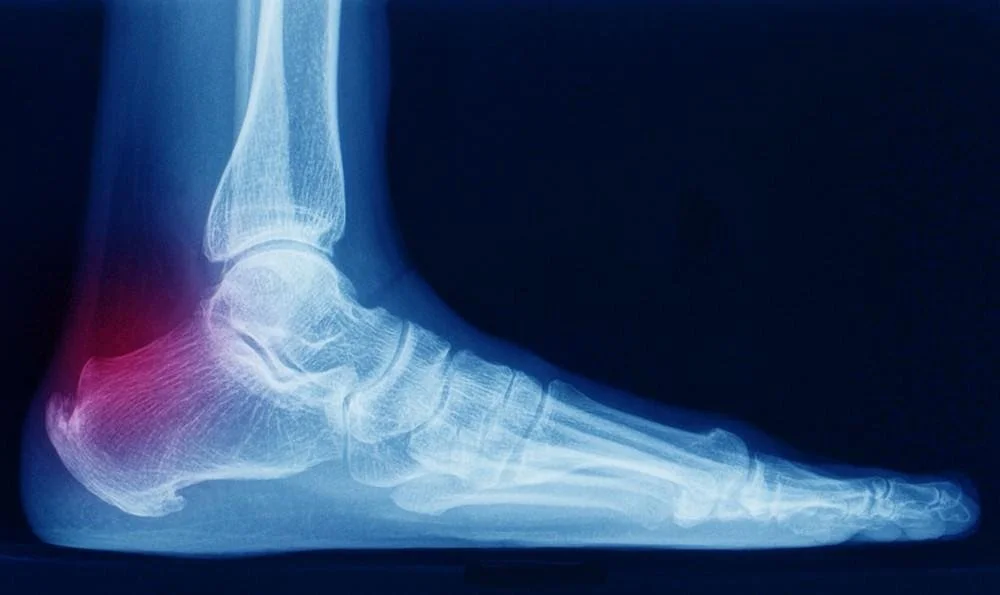

The patient came to our Sheffield physiotherapy clinic with a swollen Tendo-Achilles (TA) and it was painful for them to bear any weight on the affected left ankle (see picture, top left). They suffered significant pain when climbing stairs they really wanted to manage the condition and prevent any surgical reconstruction which would involve hospitalisation.

Before Treatment: Image shows swelling along the Achilles Tendon